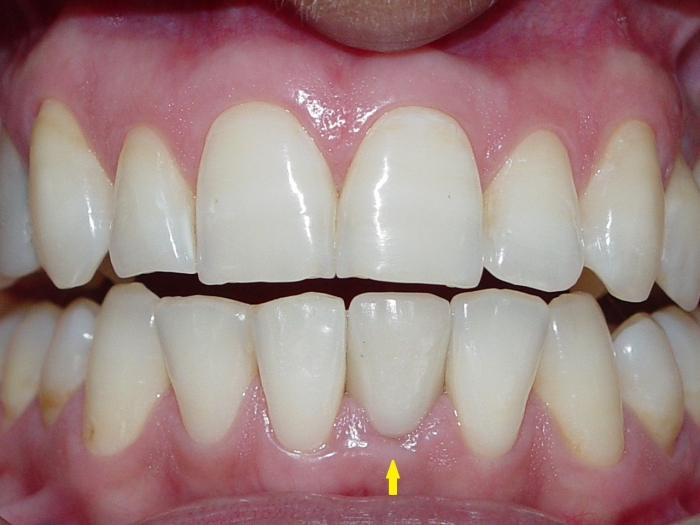

Imagens finais do caso terminado em fevereiro de 2010, com prótese em porcelana sobre implante